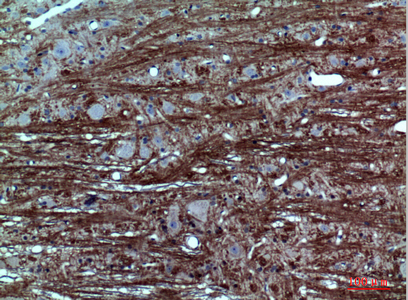

![GABA A Receptor alpha 1 antibody [N1C1] detects GABA A Receptor alpha 1 protein at cytoplasm in rat brain by immunohistochemical analysis. Sample: Paraffin-embedded rat brain. GABA A Receptor alpha 1 antibody [N1C1] (GTX104027) diluted at 1:500.

Antigen Retrieval: Citrate buffer, pH 6.0, 15 min](https://www.genetex.com/upload/website/prouct_img/normal/GTX104027/GTX104027_39925_20160309_IHC-P_R_w_23060120_899.webp)